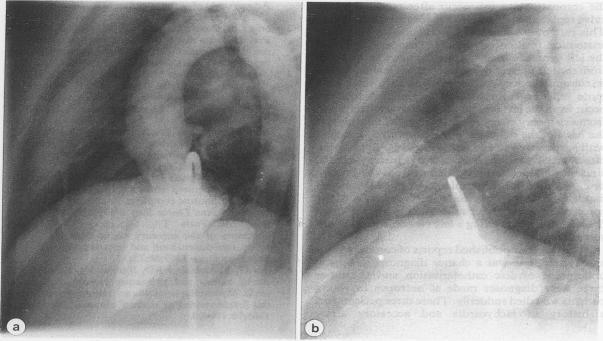

左心室与冠状窦之间的先天性瘘管:彩色多普勒血流图的阐明

Congenital fistula between the left ventricle and coronary sinus: elucidation by colour Doppler flow mapping.

A fistula between the left ventricle and the coronary sinus was diagnosed by Doppler echocardiography and confirmed by cardiac catheterisation in a symptom free child who presented with clinical signs of mitral regurgitation. A similar abnormality has been reported after repeated mitral valve replacement and after myocardial infarction but a congenital fistula of this type has not been described before.

一名二尖瓣反流临床体征明显但无症状的儿童,通过多普勒超声心动图诊断出左心室与冠状窦之间存在瘘管,并经心导管检查得以证实。此前已有报道称,在反复进行二尖瓣置换术后以及心肌梗死后会出现类似异常,但此前尚未描述过这种类型的先天性瘘管。